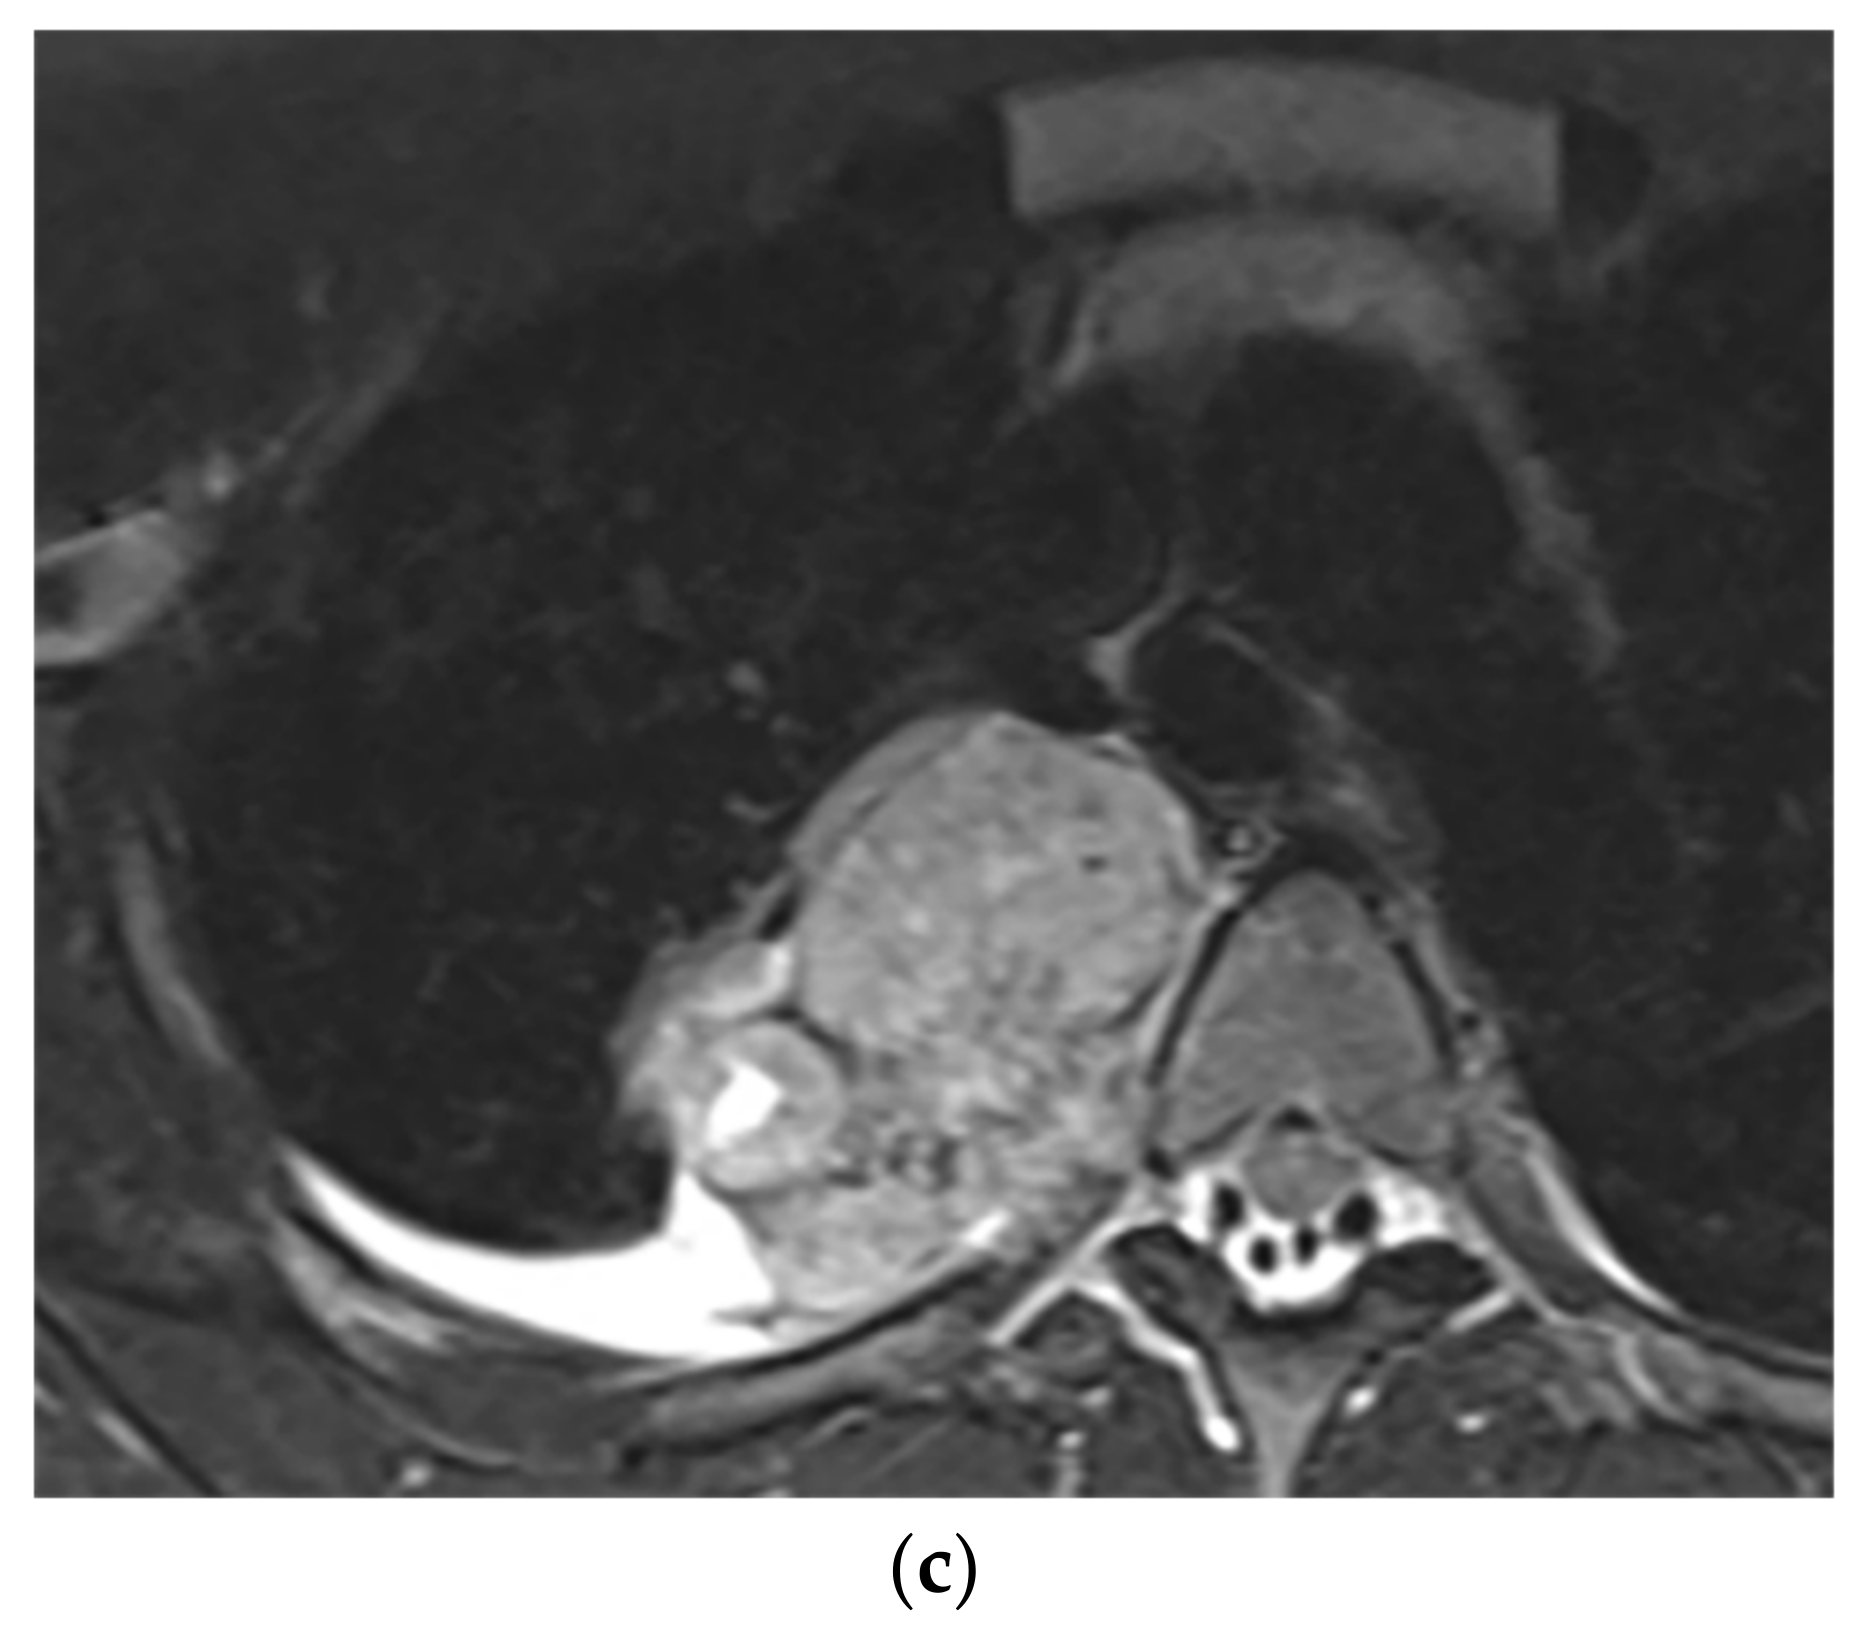

| Mesothelioma | Circumferential pleural thickening, bony or cartilaginous differentiation, unilateral pleural effusion, interlobular septal thickening, tumoral extension, thoracic and extrathoracic metastasis. | T1W: unilateral hyperintense pleural effusion, iso to slightly hyperintense pleural thickening T2W: moderately hyperintense T1WFS + C: typical enhancement is expected |